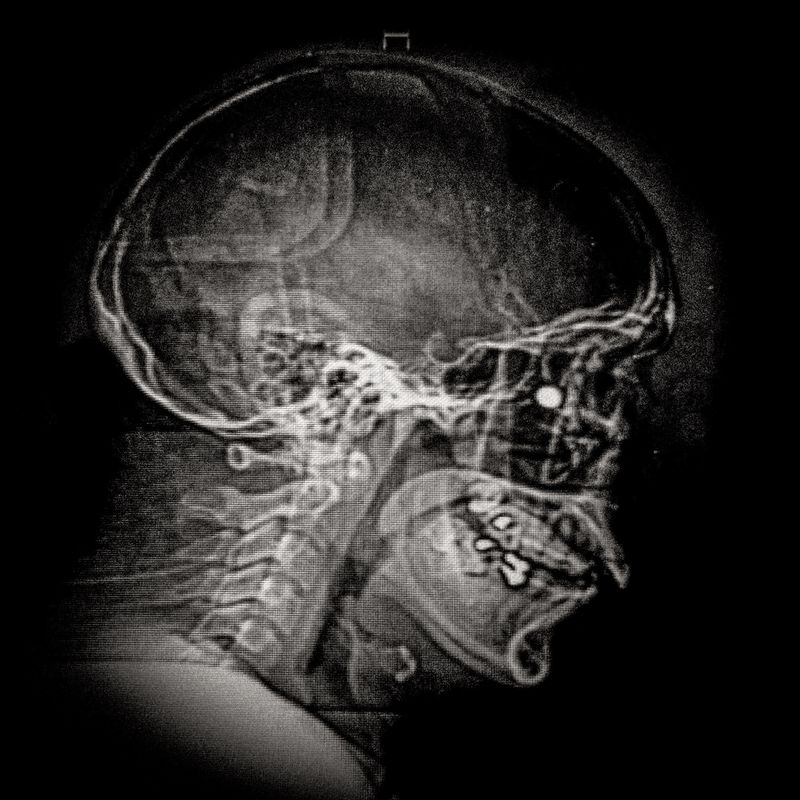

X ray showing the embedded pellet of an injured man during Santiago protests.

X ray showing the embedded pellet of Camilo Galvez (24) injured by chilean police during Santiago protests.